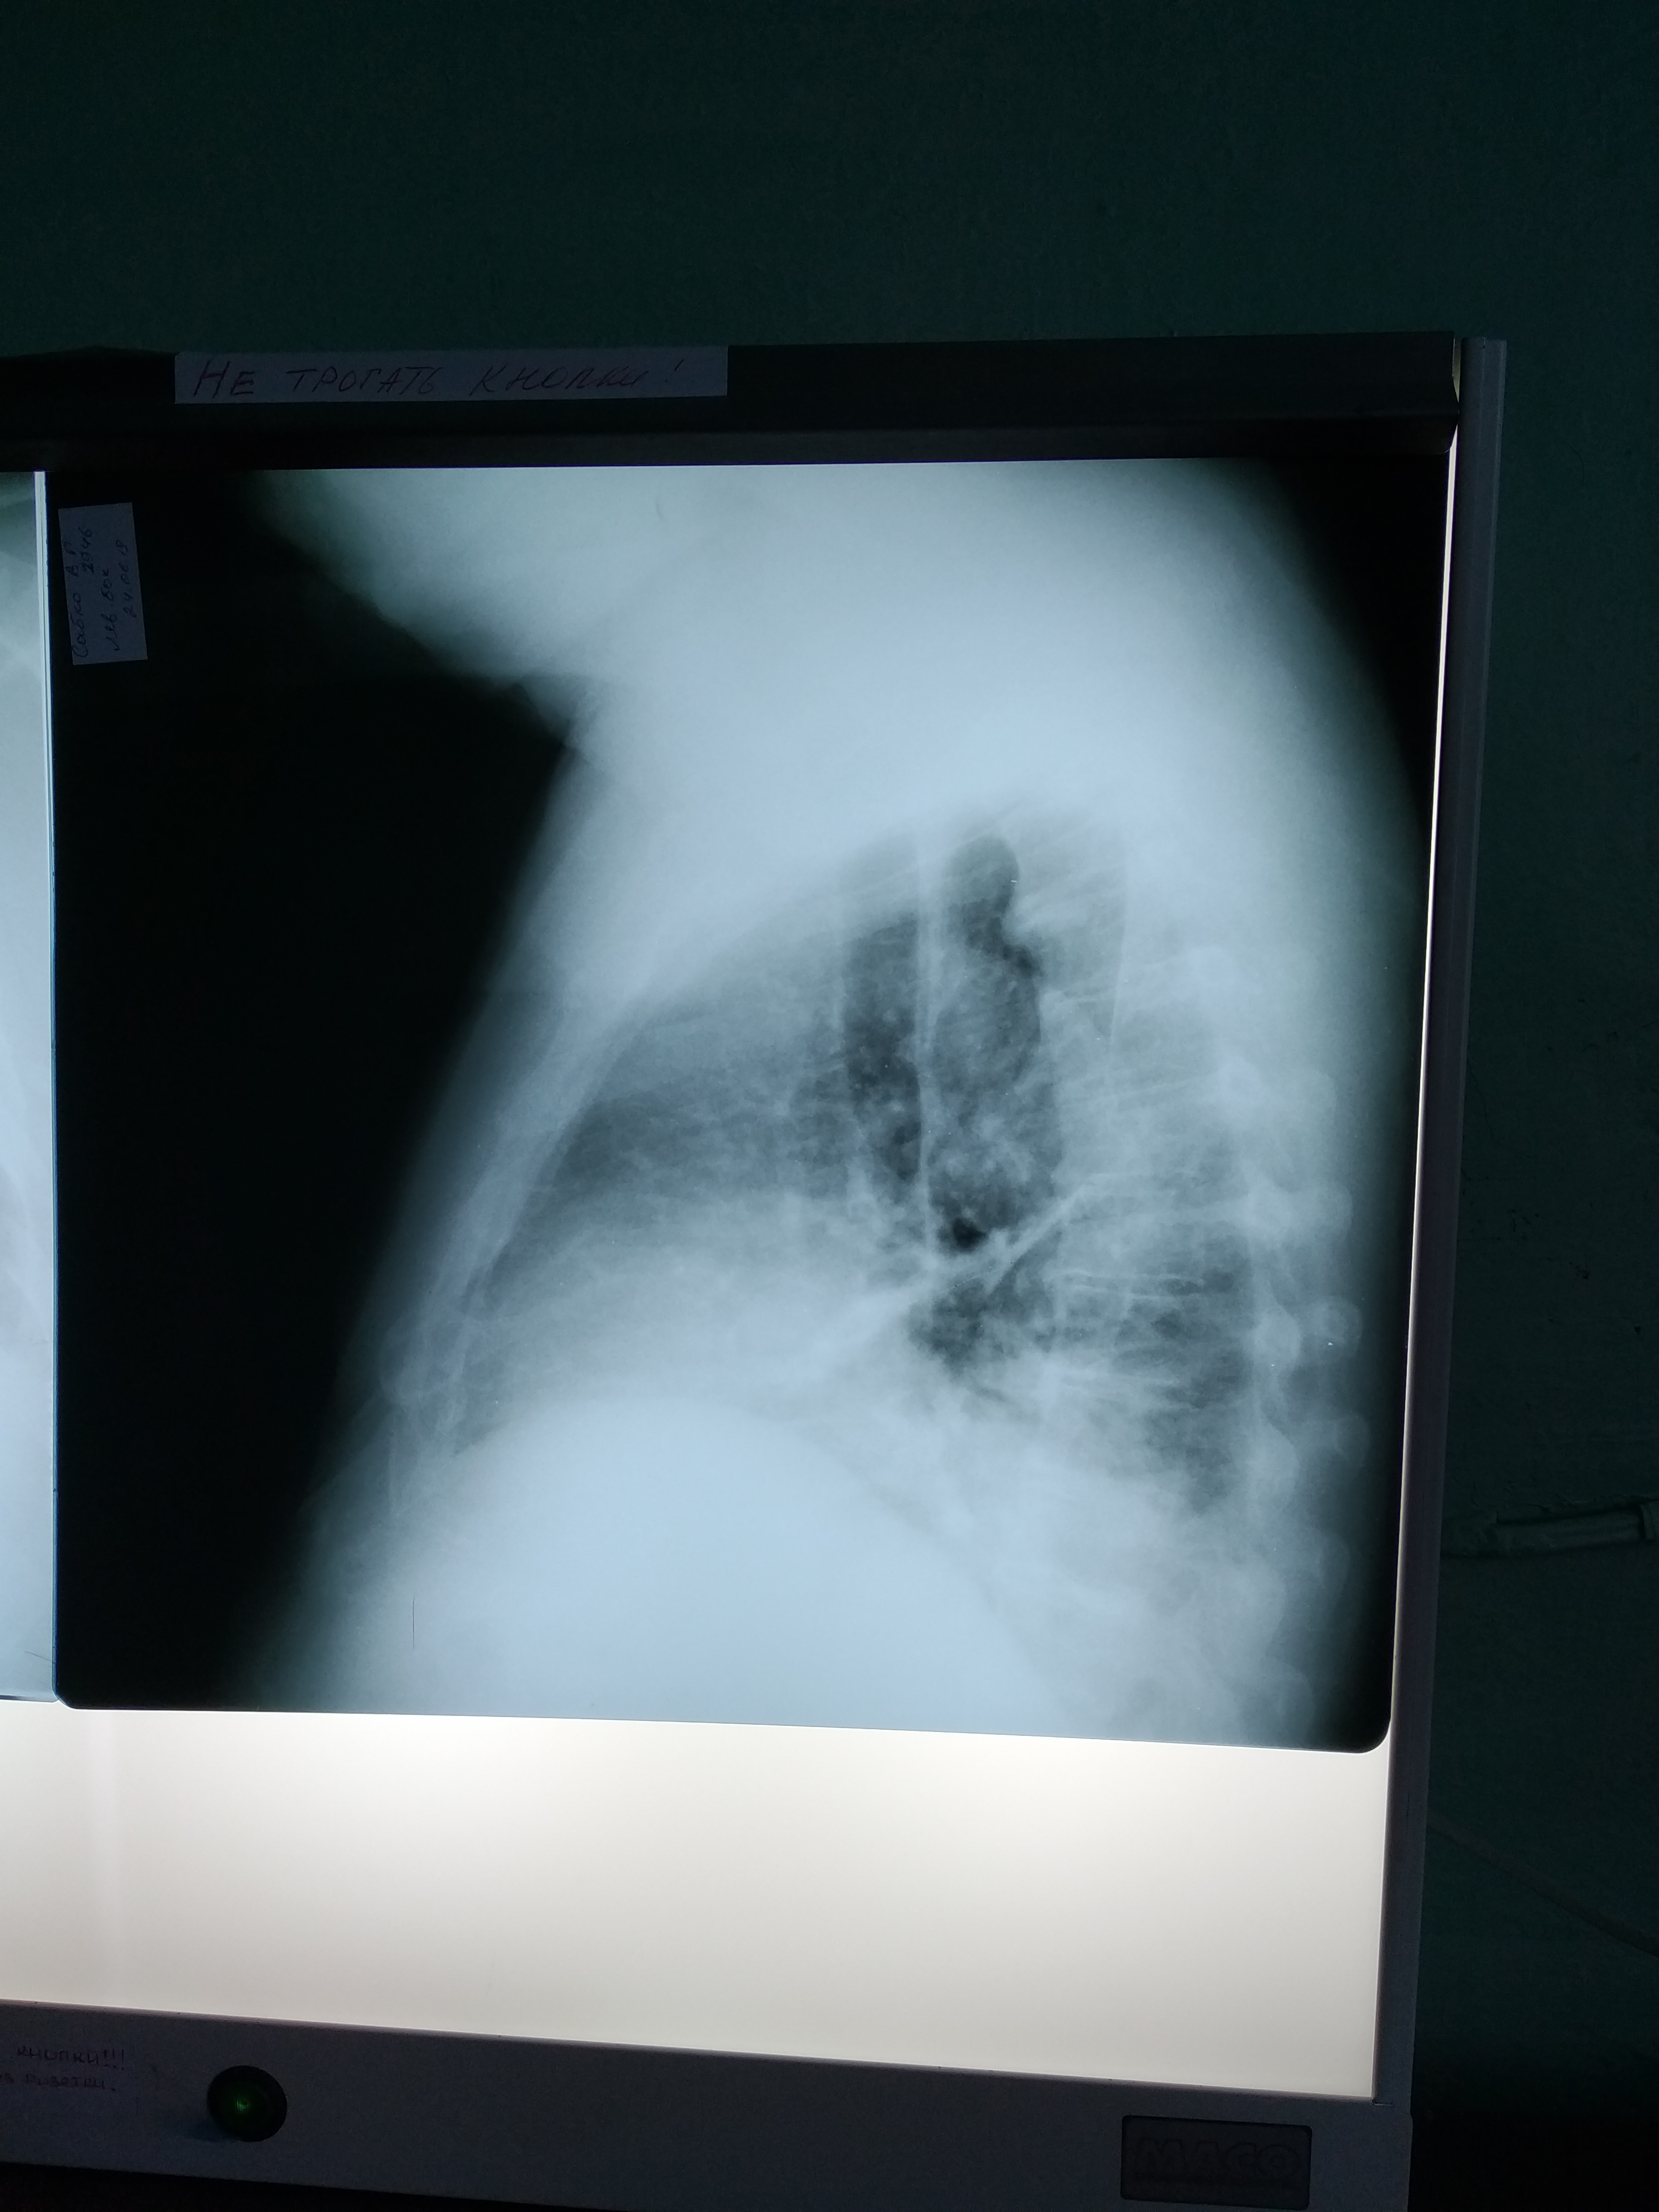

Похоже на опухоль с распадом и нагноением, ателектаз, гидроторакс/плеврит.

Рентгенограмму покажете?

Re: в плевральной полости

Завтра его повезут на КТ. Диск жена обещала купить, поэтому и КТ картинка, возможно, будет.